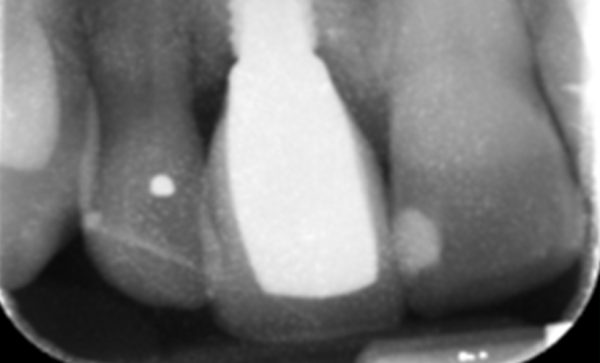

Case 5